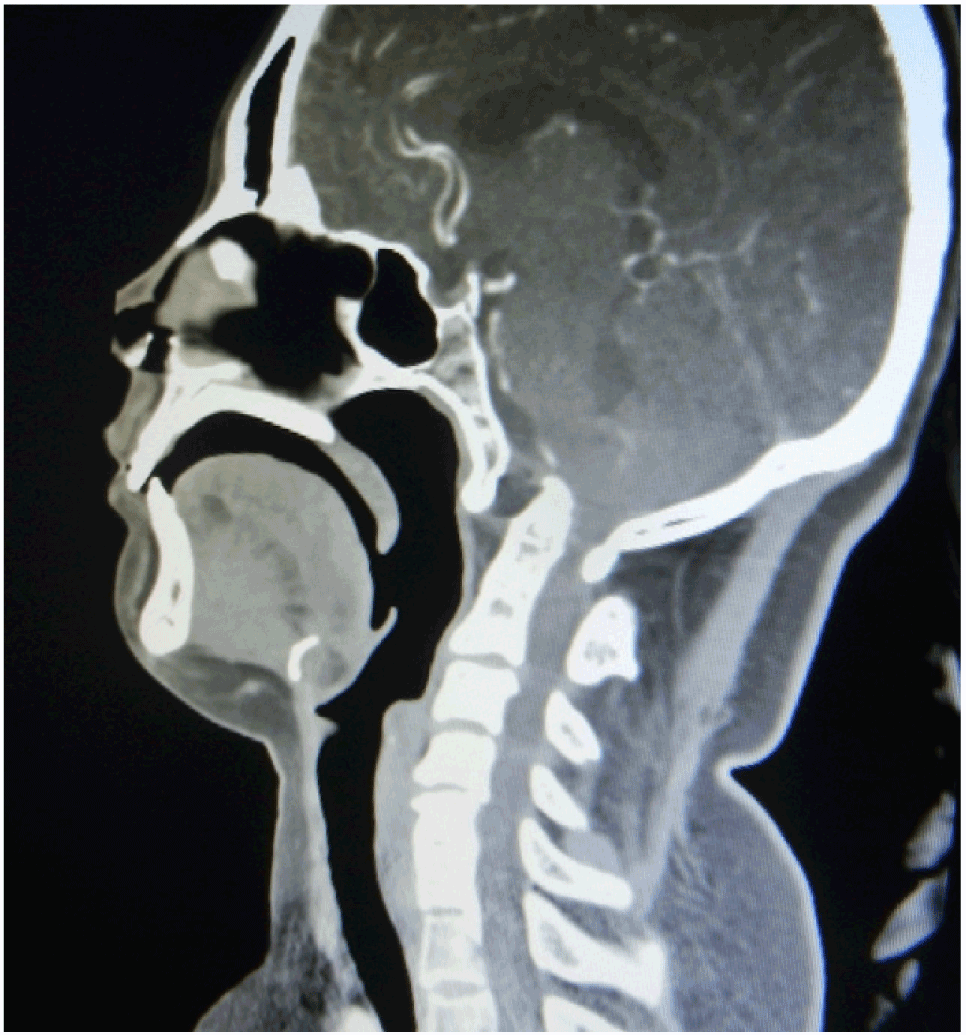

A-18-year -old college boy presented with history of insidious onset slowly progressive neck pain and difficulty in walking for 6 months. He had no past history of trauma or meningitis. General survey revealed short and webbed neck, low hair line and high arch palate. Neurological examination revealed no abnormality of cranial nerves. Muscle tones were increased in all limbs. Powers in all limbs were grade 4. All deep tendon jerks were brisk with bilateral plantar extensor response. Cerebellar signs were present. Plain x-ray of craniovertebral junction and cervical spine revealed fixed atlantoaxial dislocation with marked basilar invagination and fusion of spinous process of C 3 to C5 cervical vertebrae. CT scan revealed presence basilar invagination with Kippel -Fiel syndrome. MRI of craniovertebral junction and cervical spine revealed large tumour in the posterior fossa, showing hypointense signal on T1 weighted image compression at craniovertebral junction with intracerebellar dermoid, showing hypointense signal with basilar invagination with Kippel feil syndrome (Figure 1 and 2) and hyperintense signal on T2 weighted image, sagittal section image showing the tumour .

Figure 1. Computed tomography of cervical spine, sagittal reconstruction showing presence of basilar invagination with Kippel -Fiel syndrome